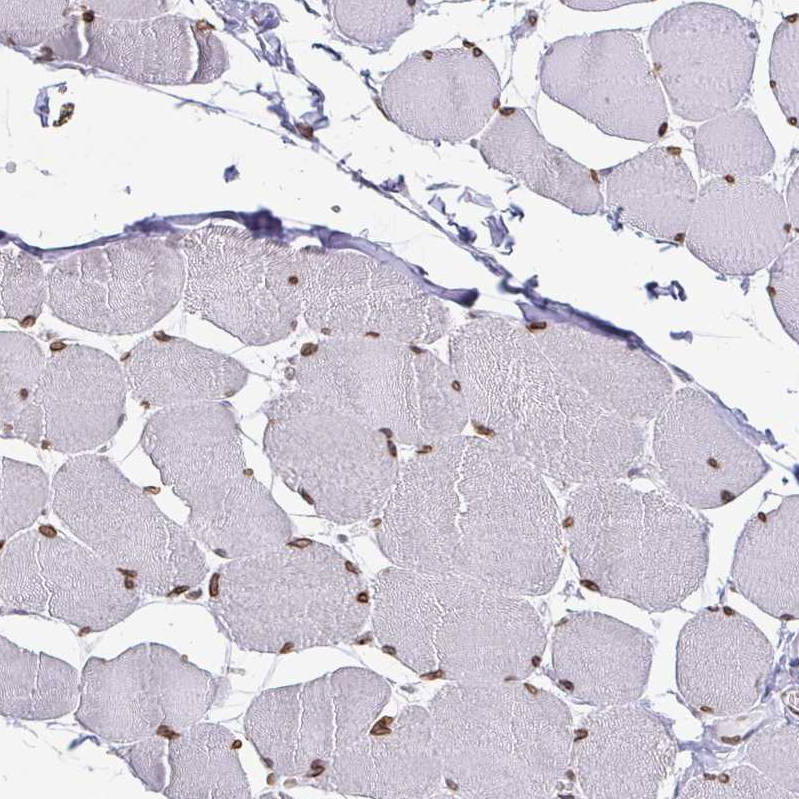

Immunohistochemical staining of human skeletal muscle shows strong positivity in nuclear membrane in myocytes.